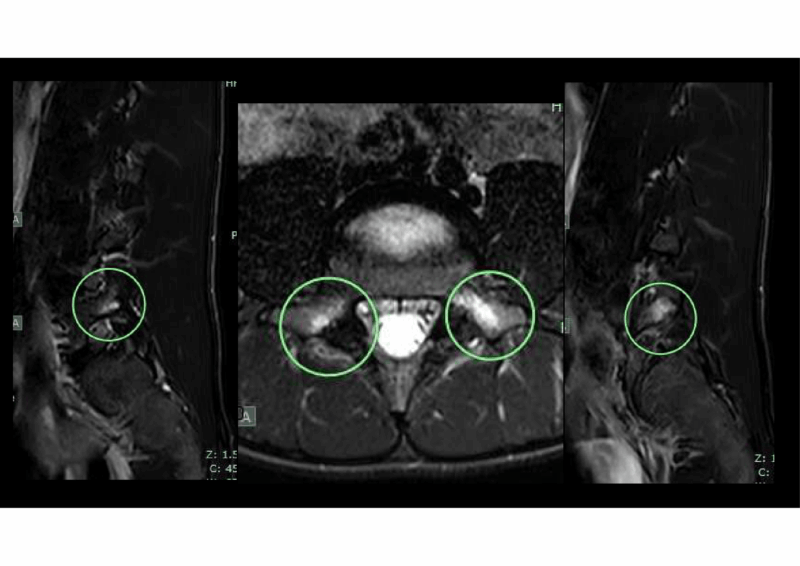

CT、MRIを即時に撮影し、受診から1時間以内で完了

CTでわずかな骨折線、MRIでは両側L5椎弓根に脂肪抑制画像で高信号を認めた。